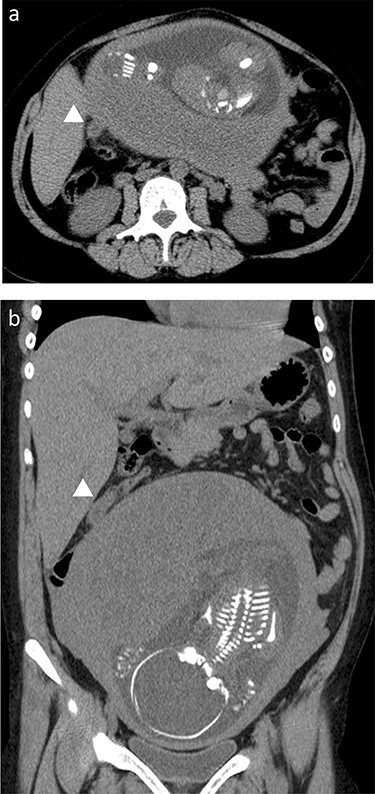

Preoperative CT scan; the swollen appendix (arrows) was translocated to the upper abdomen, and it can be observed underneath the liver, near the gallbladder; (a) axial view, (b) coronal view.

A 31-year-old pregnant female at 27 weeks gestational age visited our hospital with symptoms of acute epigastralgia, which had moved down to the right lower intestinal quadrant, and vomiting. She was gravida 8 and para 7, with no history of abdominal surgery. The blood exam showed an elevated white blood cell count (17 200/μl) and a high C-reactive protein level (2.01 mg/dl). The appendix could be detected with abdominal ultrasonography; it was inflamed and swollen to a length of 12 mm. A computed tomography (CT) scan was performed to confirm the degree of appendix inflammation and its location, showing the dirty fat sign and a swollen appendix located underneath the liver, close to the gallbladder fundus (Fig. 1a and b). The patient was clinically diagnosed with acute appendicitis. An emergency laparoscopic appendectomy was performed with the RPLA approach.